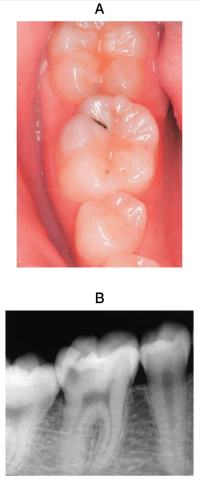

15 歳の男子。下顎右側第一大臼歯の違和感を主訴として来院した。歯髄電気診に生活反応を示すが、打診痛はない。コンポジットレジン修復を行うこととした。初診時の口腔内写真、エックス線画像及び器具の写真を別に示す。